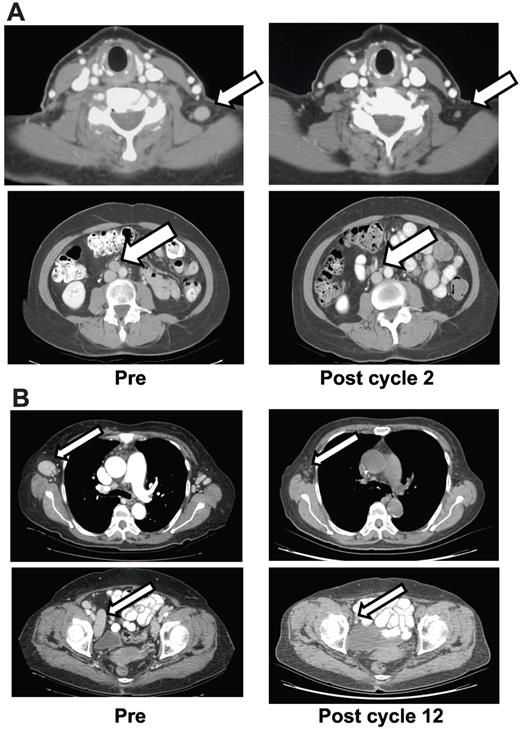

Complete responses were noted in 8 patients (18%) with a median duration of response of 29.7 months (range 3-74). Three patients remain on protocol with 2 continuing in CR. The third patient experienced re-emergence of disease 74 months after achieving a CR (53 months after discontinuing therapy) and has restarted therapy as allowed by protocol. Responses in 2 of these patients are shown in Figure 1A and B. A fourth patient, 84 years old, died because of worsening of his pre-existing aortic stenosis 14 months after discontinuing romidepsin. One patient discontinued study because of progression of disease, and 1 patient died unexpectedly, as noted above. A seventh patient, discussed in “Toxicities,”, developed a new EBV-positive NK-T lymphoma. The eighth patient was noted to have elevated LFTs on routine laboratory evaluations after 11 cycles of therapy. Evaluation demonstrated a reactivation of hepatitis B. Details of these latter 2 patients have been reported.27

Patient responses. (A) Patient had recurrent PTCL, subtype not otherwise specified (NOS) after cyclophosphamide, doxorubicin, vincristine, and prednisone (CHOP); etoposide, methylprednisolone, cytarabine, and cisplatin (ESHAP); and autologous stem cell transplant. PET scan at 8 months showed no evidence of disease. The response was scored as CR and therapy was discontinued after 2 years with the patient remaining free of disease for another 53 months. (B) Patient with PTCL, subtype not otherwise specified (NOS), had prior CHOP and pralatrexate. Patient, who was declared a PR after 2 cycles of romidepsin and a CR afer 12 cycles of romidepsin, remained on study at 24 months as of data cutoff.